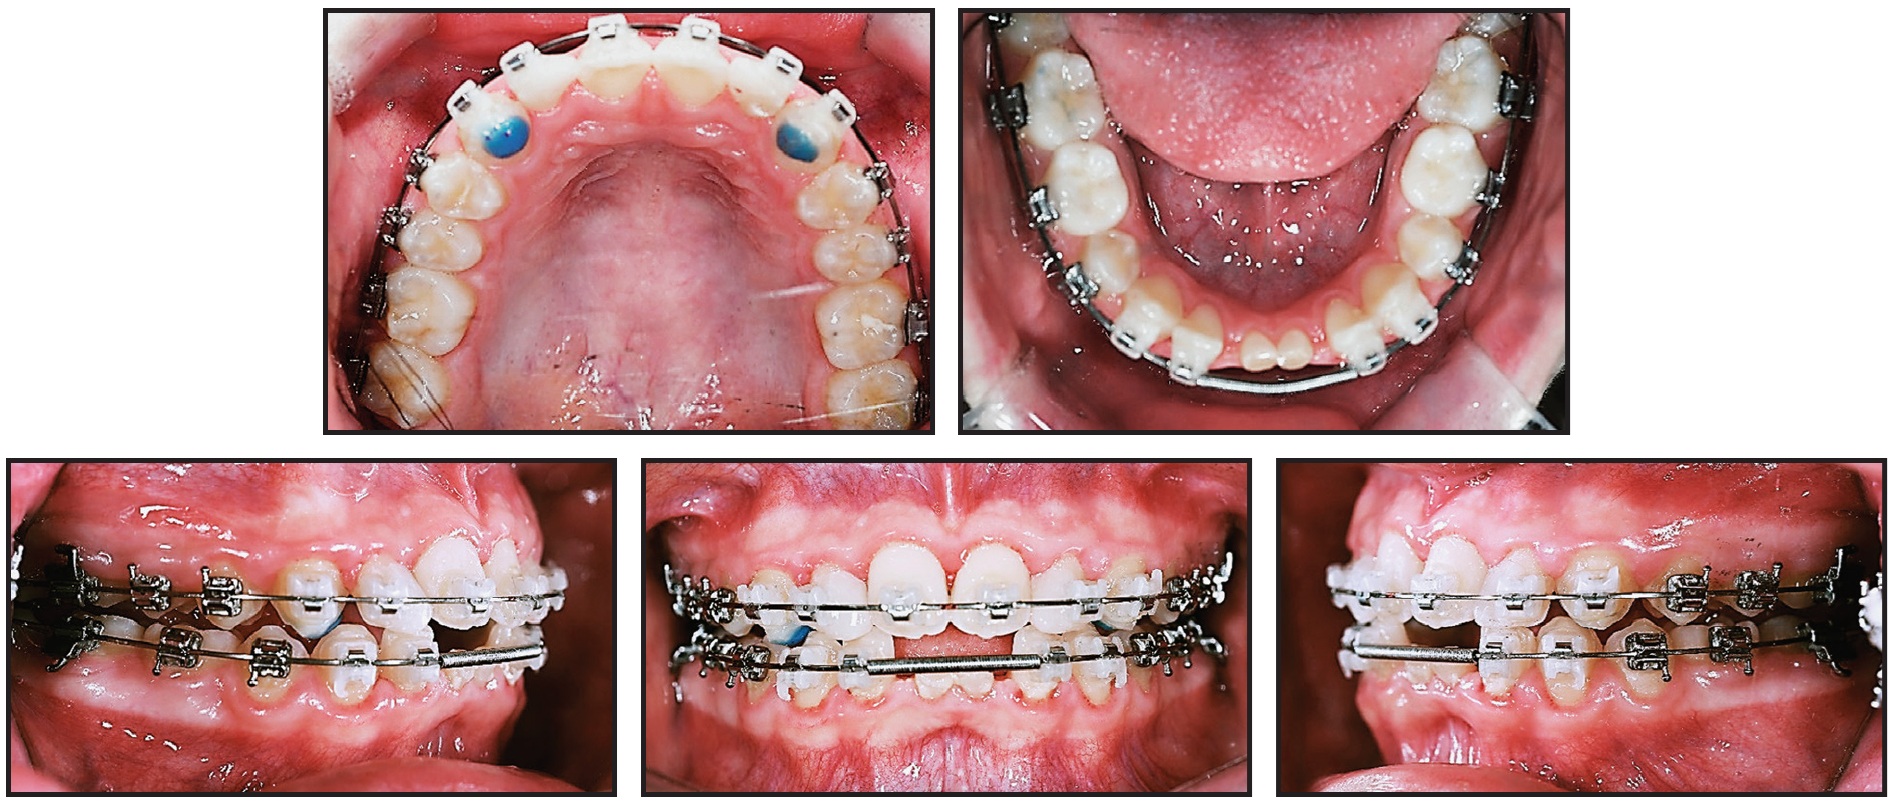

Both arches were bonded with .022" Tweemac-prescription Quicklear*** brackets. After 24 months of orthodontic treatment, the overjet and overbite were corrected, and Class I canine and molar relationships were achieved (Fig. 5).

Fig. 5 After 24 months of treatment with .022" Tweemac-prescription Quicklear*** brackets, anterior deep bite corrected and space gained for restoration of lower central incisors.

A 13-year-old female presented with an anterior deep bite, congenitally missing lower permanent central incisors and second premolars, and a skeletal Class II relationship (Fig. 4). We planned to use nonextraction treatment to correct the skeletal discrepancy.

Fig. 4 13-year-old female patient with anterior deep bite, congenitally missing lower permanent central incisors and second premolars, and skeletal Class II relationship before treatment.